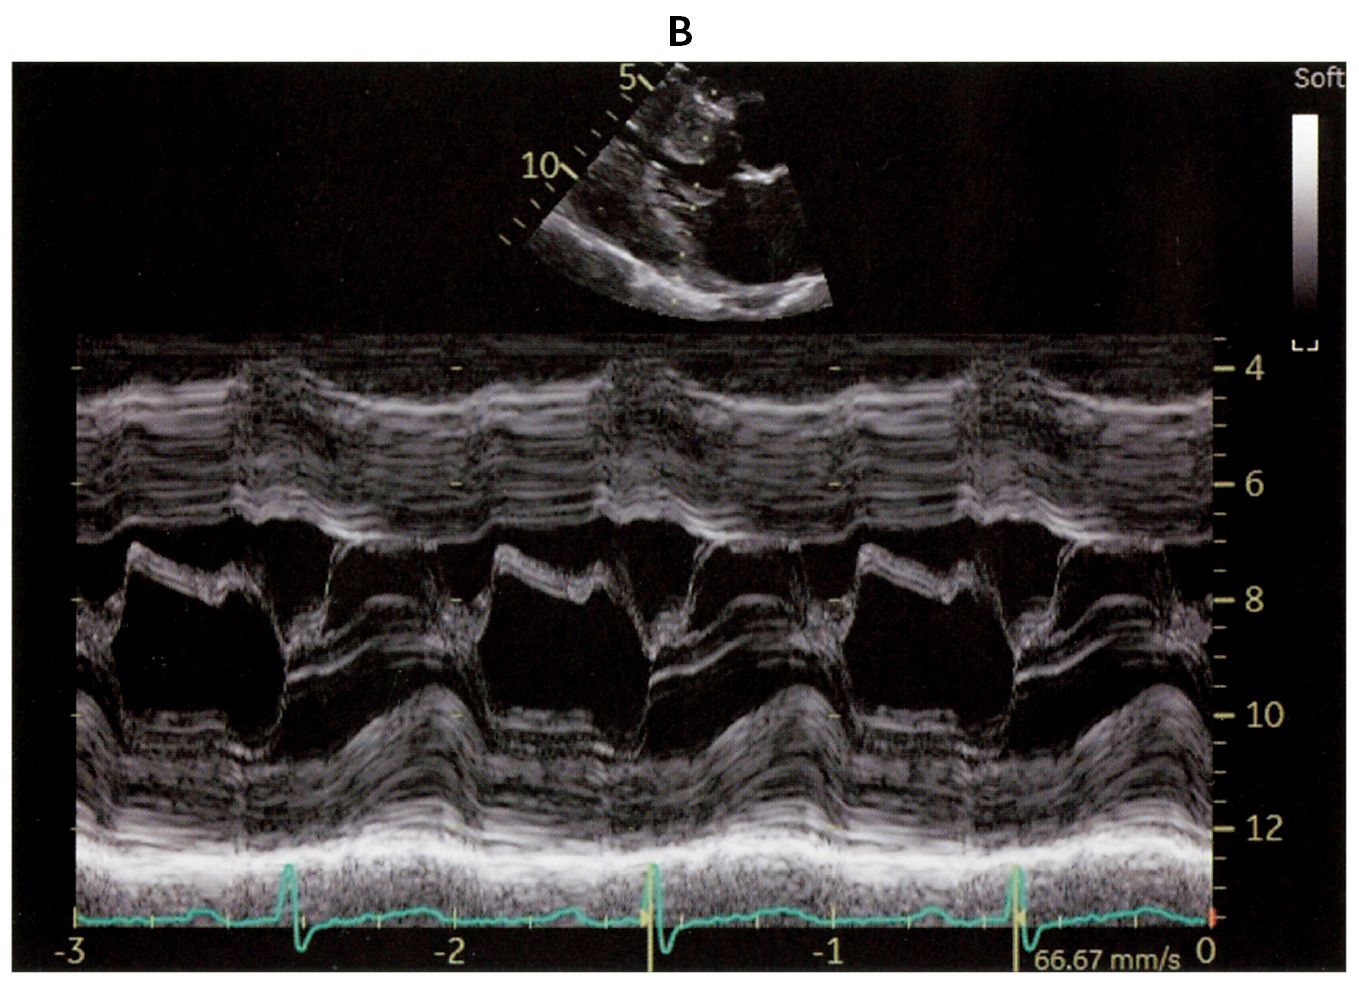

54歳の男性。労作時の息切れを主訴に来院した。以前から心電図異常を指摘されていたが精査は受けていなかった。身長172cm,体重64kg。体温36.5℃。脈拍72/分,整。血圧130/80mmHg。呼吸数18/分。頸静脈の怒張は認めない。胸骨左縁第4肋間を中心にLevine 4/6の収縮期雑音とⅣ音を聴取する。呼吸音に異常を認めない。腹部は平坦,軟で,肝・脾を触知しない。下肢に浮腫を認めない。心エコー検査の傍胸骨長軸像(A)とMモード(B)とを下に示す。